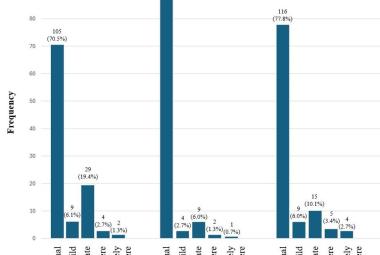

Parkinson’s disease (PD) is a neurological condition affecting the motor functions of the brain, characterised by the degeneration of dopaminergic neurons in the substantia nigra pars compacta region. The primary symptoms include dyskinesia, bradykinesia and resting tremors. This study investigated the potential impacts of Mitragyna speciosa or known as kratom on zebrafish with PD. 1-methyl-1,2,3,6-tetrahydropyridine (MPTP) solution was administered intraperitoneally to zebrafish to develop Parkinson’s symptoms in 2 to 3 days, followed by three concentrations treatment of kratom, for 28 days. On day 28, locomotor behaviour was evaluated to determine the duration spent in the top, middle, and bottom zones, total distance travelled and swimming speed. Then, the zebrafish were euthanised and preserved in a 10% formalin solution. Fixed zebrafish were processed and embedded in paraffin blocks for haematoxylin and eosin, and cresyl violet staining. The results of treatment groups showed that kratom had a neuroprotective impact, increasing time spent from bottom to top zone, distance travelled and swimming speed compared to the negative group. Moreover, the treatment groups experienced a rise in neuron regeneration and an enhancement in neuron appearance following a 28-day exposure to kratom. In conclusion, kratom shows promise as a potential treatment for PD by effectively reducing symptoms and improving movement.